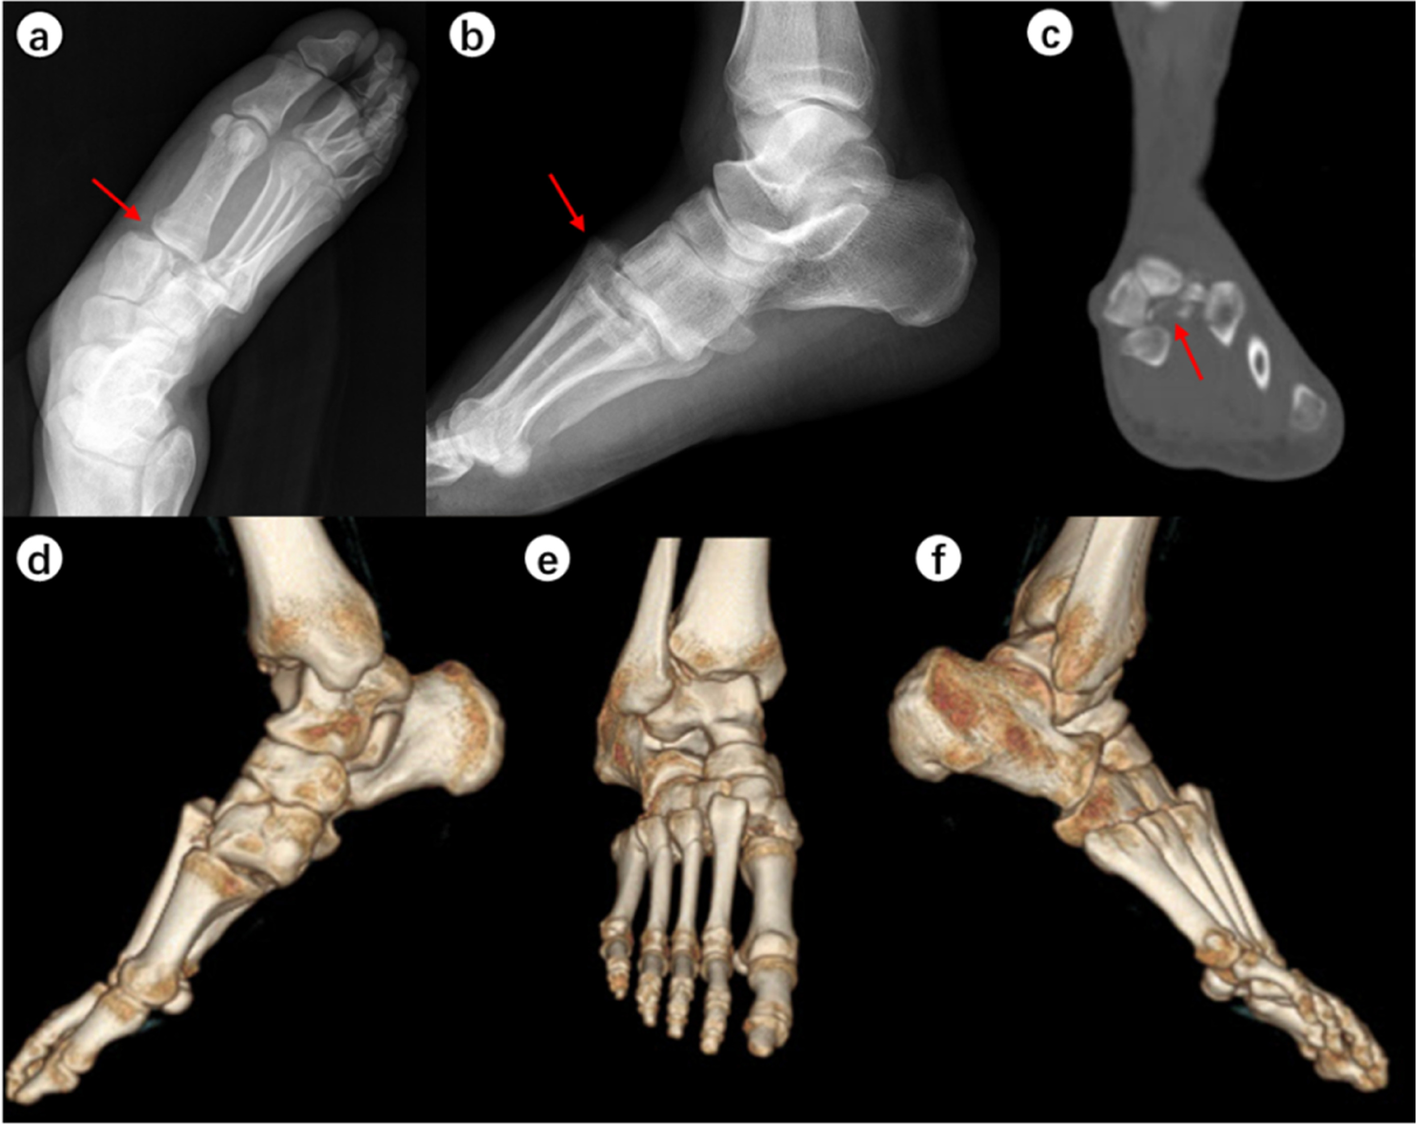

When the surgeons were asked to re-evaluate their initial treatment strategies after assessing the CT images (Table 5), the mean alteration rate was 21.9% (observer A, 28.3%; observer B, 15.6%). This represented a significant difference in alteration rates between the two observers (p < 0.001). Typical case images are shown in the figures (Figs. 1, 2, 3 and 4).

A 37-year-old man fell and hurt his left foot. Chiodo-Myerson’s classification: medial–lateral-column injury; Displacement classification: displaced injury. Both two observers made the correct diagnosis for two times, and didn’t change the initial treatment option (surgery) after evaluating CT image. a-c The conventional radiographs showed no obvious fractures. The separation of the first and second rays strongly suggested Lisfranc injury (red arrows). d-f Computed tomography imaging showed intra-articular avulsion fractures of the medial cuneiform and fourth metatarsal bones. Red arrows indicate the fracture fragments